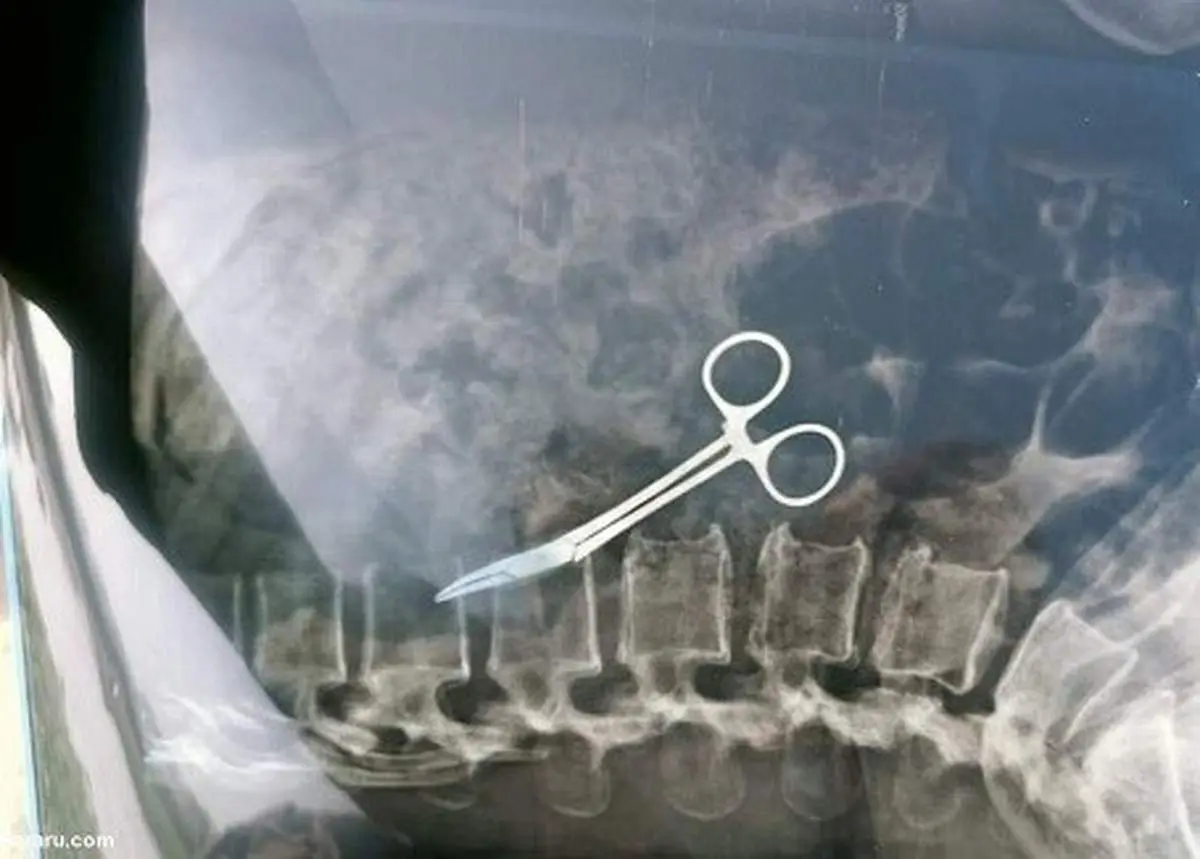

یک زن در بنگلادش که در سال ۲۰۰۲ عمل برداشتن کیسه صفرا را انجام داده بود، دائما از درد شکم رنج میبرد تا اینکه پس از ۲۰ سال مشخص شد یک قیچی جراحی در شکمش جا مانده است.

به گزارش منیبان؛ جراحان در بنگلادش یک قیچی را که ۲۰ سال پیش در داخل شکم یک زن باقی مانده بود، طی یک عمل جراحی برداشتند.

او توضیح داد: اخیراً وقتی او به ما مراجعه کرد، درخواست عکسبرداری با اشعه ایکس کردیم که در نهایت وجود قیچی داخل شکم او مشخص شد.